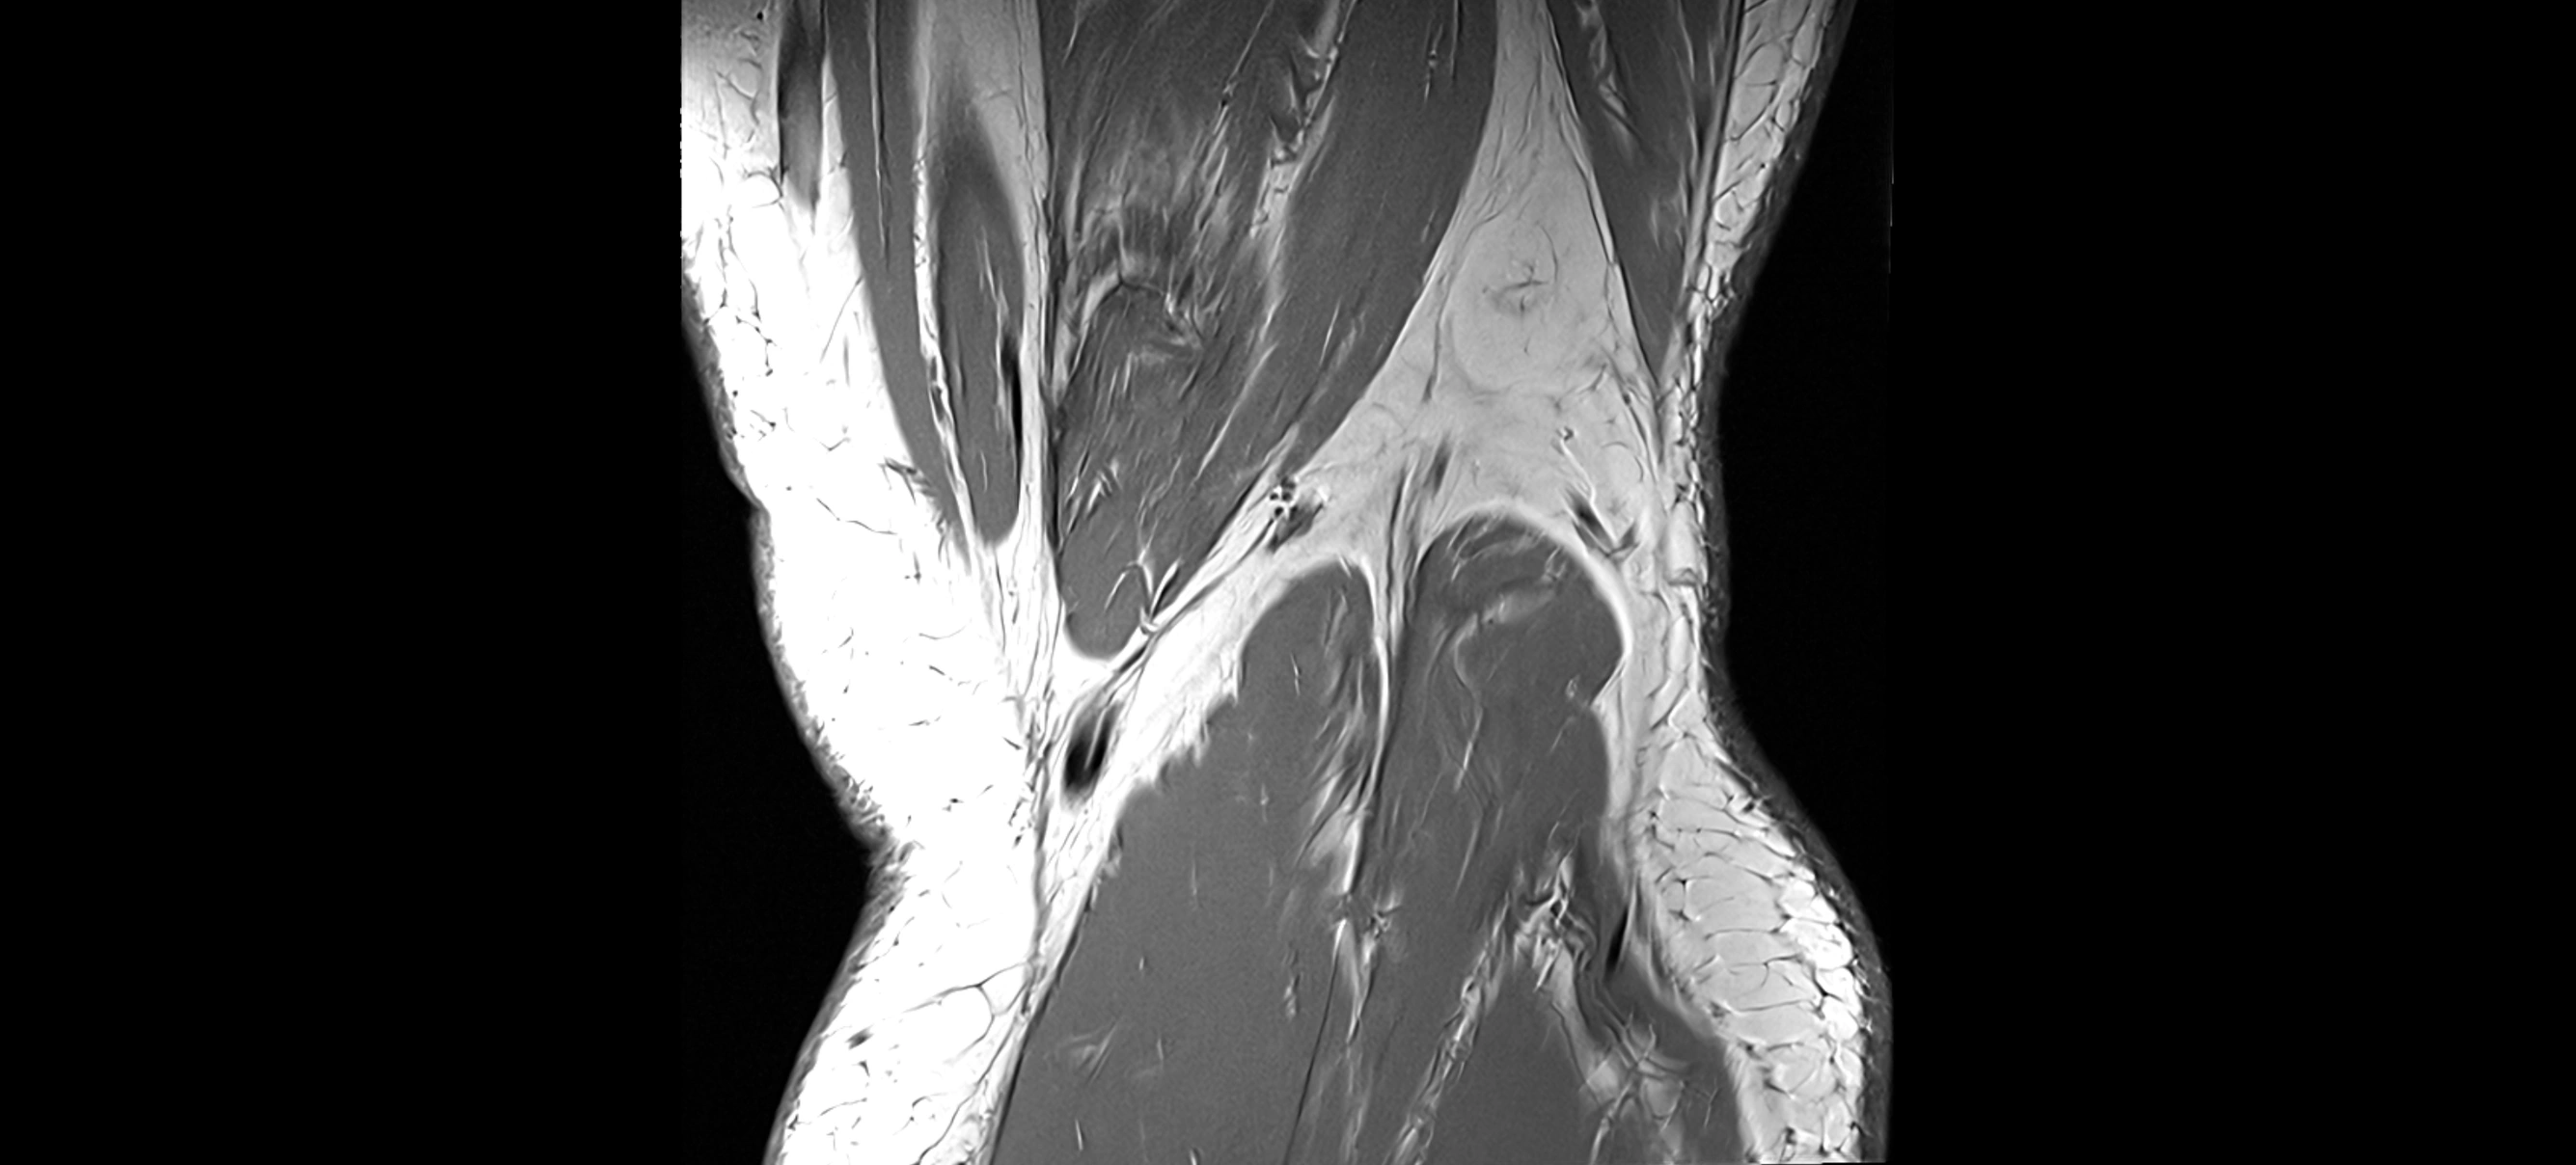

MRI images

image